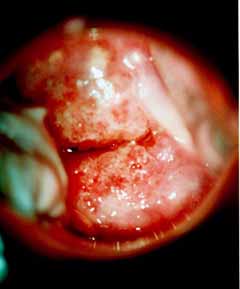

Κολποσκοπικές εικονες για τις αναγκες του forum.